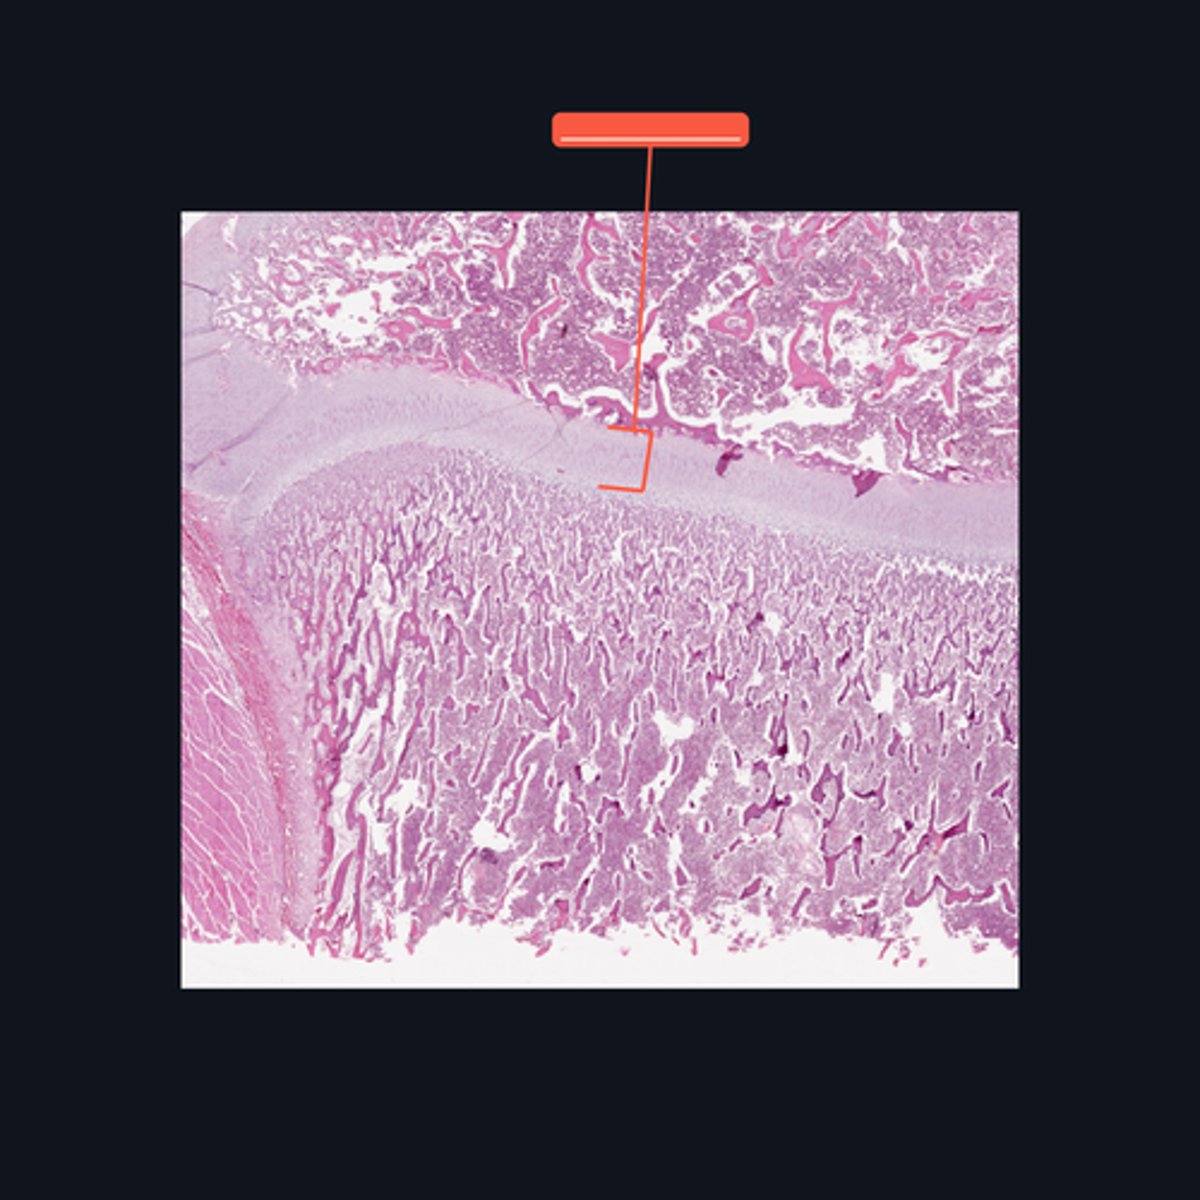

Identify what part of a typical long bone is encompassed by the bracket symbol. It is also known as the _____ of a long bone.

Medullary cavity

Identify the area encompassed by the bracket symbol, which is a hollow core that contains the developing blood cells and spongy bone spicules.

Proximal epiphysis; hyaline cartilage

Identify what part of a typical long bone is encompassed by the bracket symbol. What type of cartilage is it made up of?